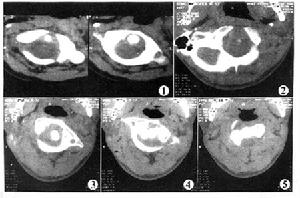

寰樞關節脫位2、CT檢查:

可與寰椎椎弓骨折及上頸椎畸形等疾病相鑑別,特別在頸部有創傷史,有頸部疼痛,僵硬或固定體位。而x線未發現異常時,CT檢查有助於防止漏診。

顱骨牽引1、如果是部分撕裂,通常採取顱骨牽引,或枕頜帶牽引重量1-3kg,牽引3周后即予頭頸胸石膏固定。